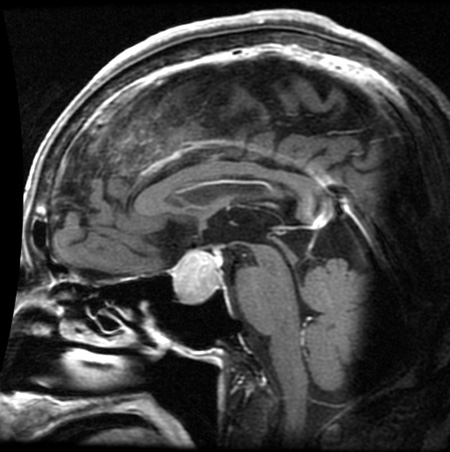

【頭蓋咽頭腫】

胎生期(生まれる前)に咽頭粘膜(喉の粘膜)が中枢神経系に迷入し、大人になってから腫瘍化することで生じると考えられています。

トルコ鞍内から鞍上部にかけて発生しますが、鞍上部に発生することが一般的です。

小児、成人ともに発生する腫瘍です。(画像所見や病理組織所見は若干異なることが多い腫瘍です)